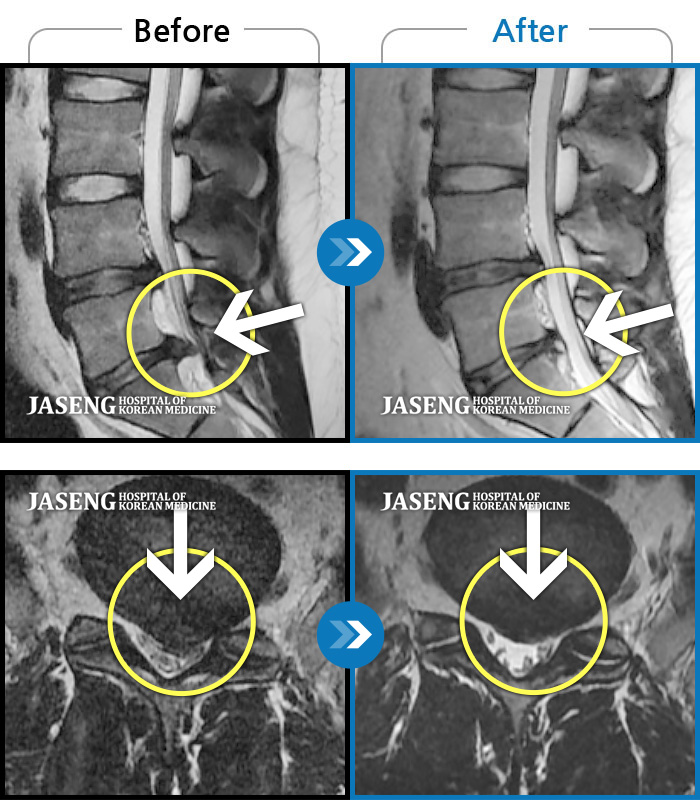

기침하다가 주저앉았어요. 지금은 양측 다리가 당겨요.